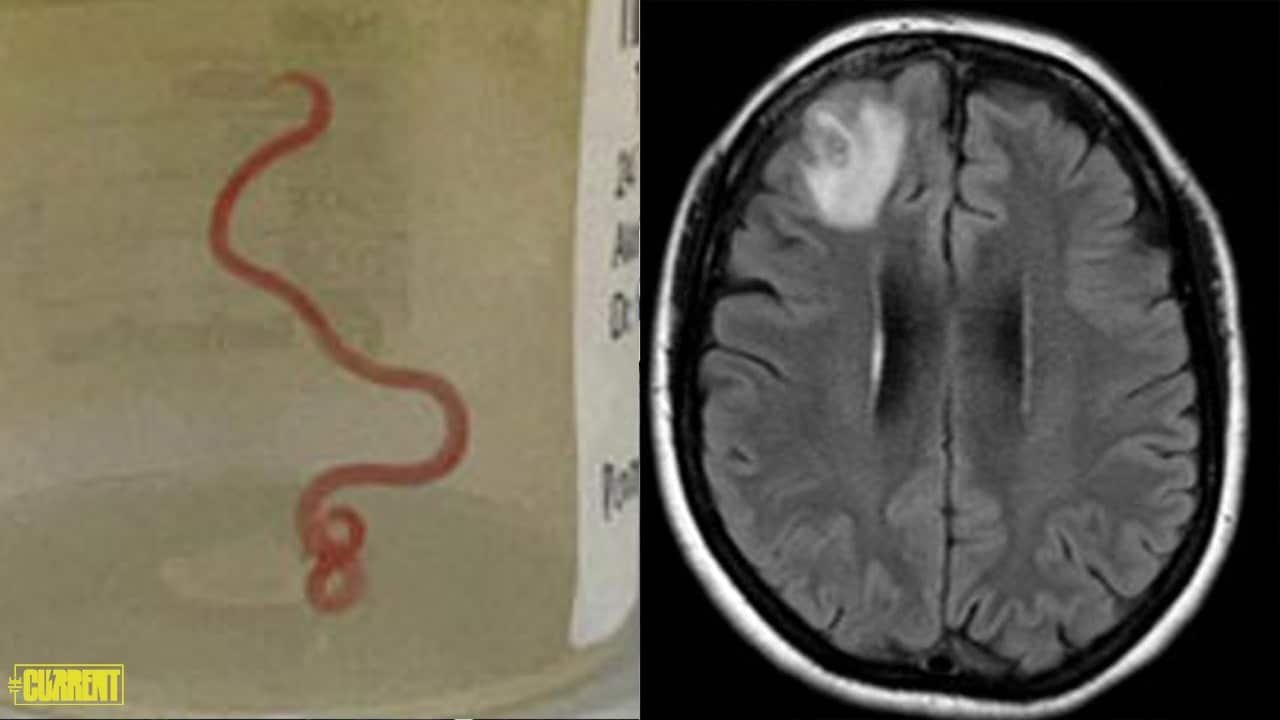

During an MRI scan of her brain, it was revealed that a living parasite, motilehelminth, was embedded in the right frontal lobe lesion of her brain, the first such instance seen in the world.

Surgical intervention was deemed necessary. After that, doctors successfully removed the 8 cm (80mm) long 1mm wide worm from her brain.

The parasite was identified as a third-stage larva of the Ophidascaris Roberts nematode species.